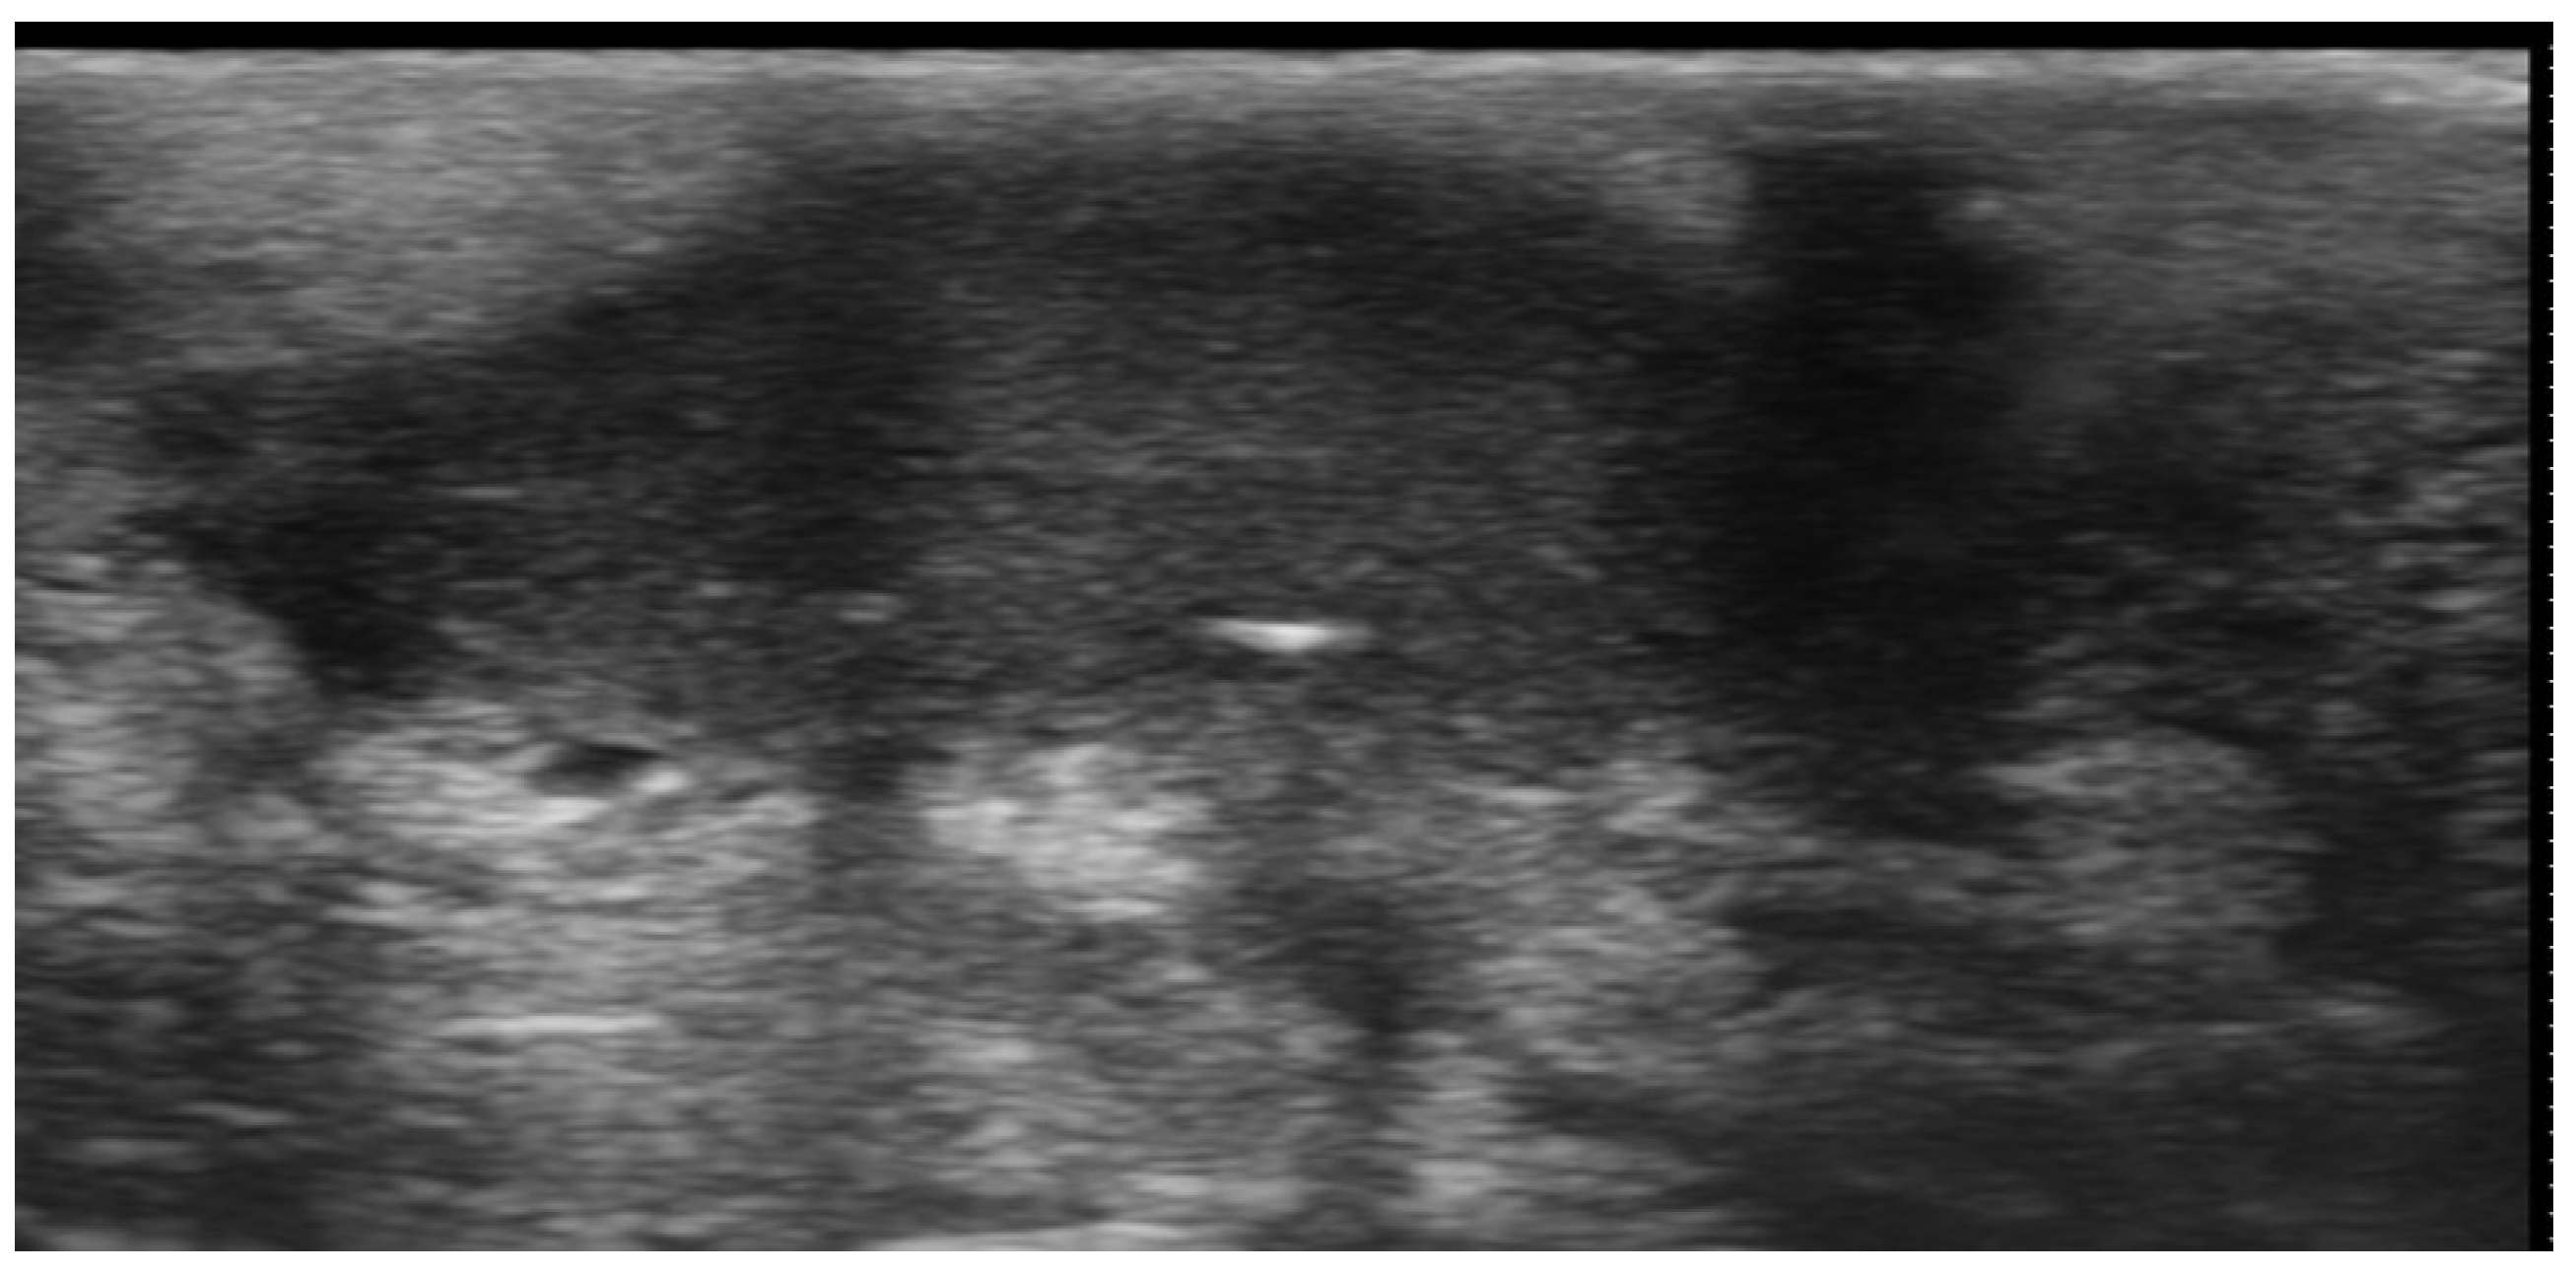

- Granieri, G.; Michelucci, A.; Manzo Margiotta, F.; Cei, B.; Vitali, S.; Romanelli, M.; Dini, V. The Role of Ultra-High-Frequency Ultrasound in Pyoderma Gangrenosum: New Insights in Pathophysiology and Diagnosis. Diagnostics 2023, 13, 2802. [Google Scholar] [CrossRef] [PubMed]